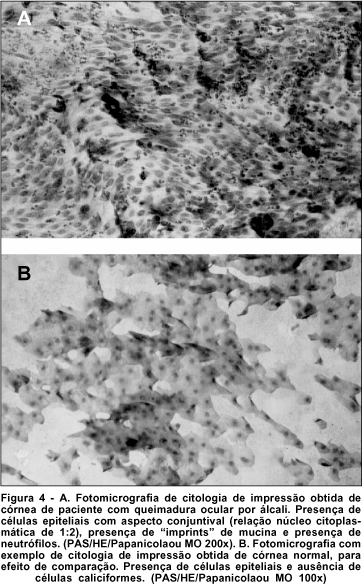

O ácido periódico de Schiff (PAS) corou as células caliciformes da conjuntiva de róseo, o que possibilitou identificar seu núcleo acêntrico e seu grande tamanho. As células epiteliais da conjuntiva são menores, com núcleo basofílico e coram-se em roxo devido à hematoxilina.

Sob microscopia óptica e com aumentos variados, analisou-se cada lâmina quanto à presença ou ausência de células caliciformes, e morfologia de células epiteliais. A amostra ideal, considerando-se que houve boa colheita e coloração padronizada, apresentou um número adequado de células morfologicamente bem preservadas, o que permitiu se observar, à microscopia óptica, a anatomia das células relativas à área desejada. (Figuras 3 e 4).